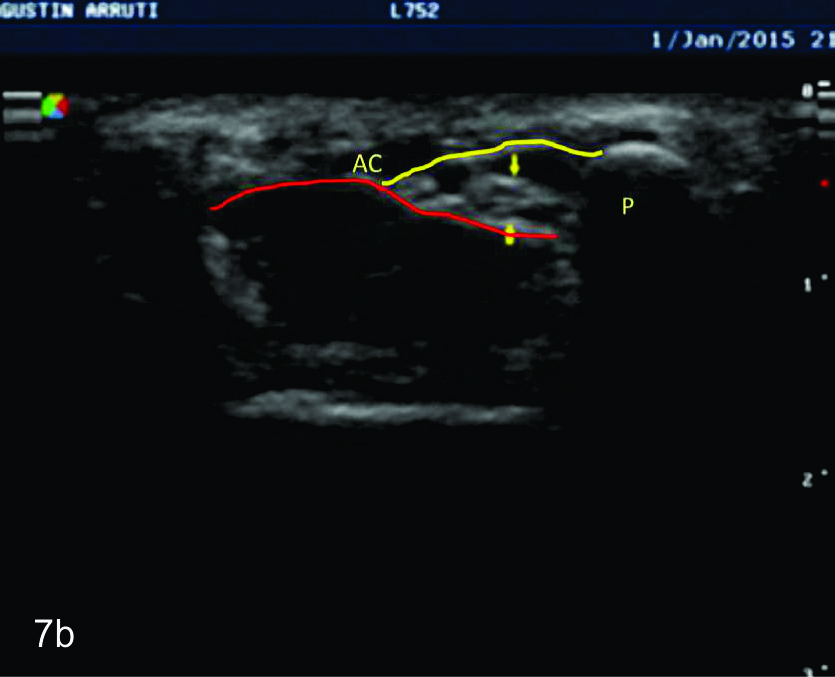

Figura 7

Nervio cubital

Serie de cortes axiales del nervio cubital desde su origen a nivel del hueco axilar hasta su terminación a nivel del canal de Guyon. Se identifica el mismo señalado por flechas amarillas y con las letras NC. AH-arteria humeral, PC- músculo prondador cuadrado, P- hueso pisciforme, Línea roja- ligamento anular del carpo, Línea amarilla- túnel de Guyon, Flecha azul- Arteria cubital-. A-tercio distal antebrazo, B- canal de Guyon.